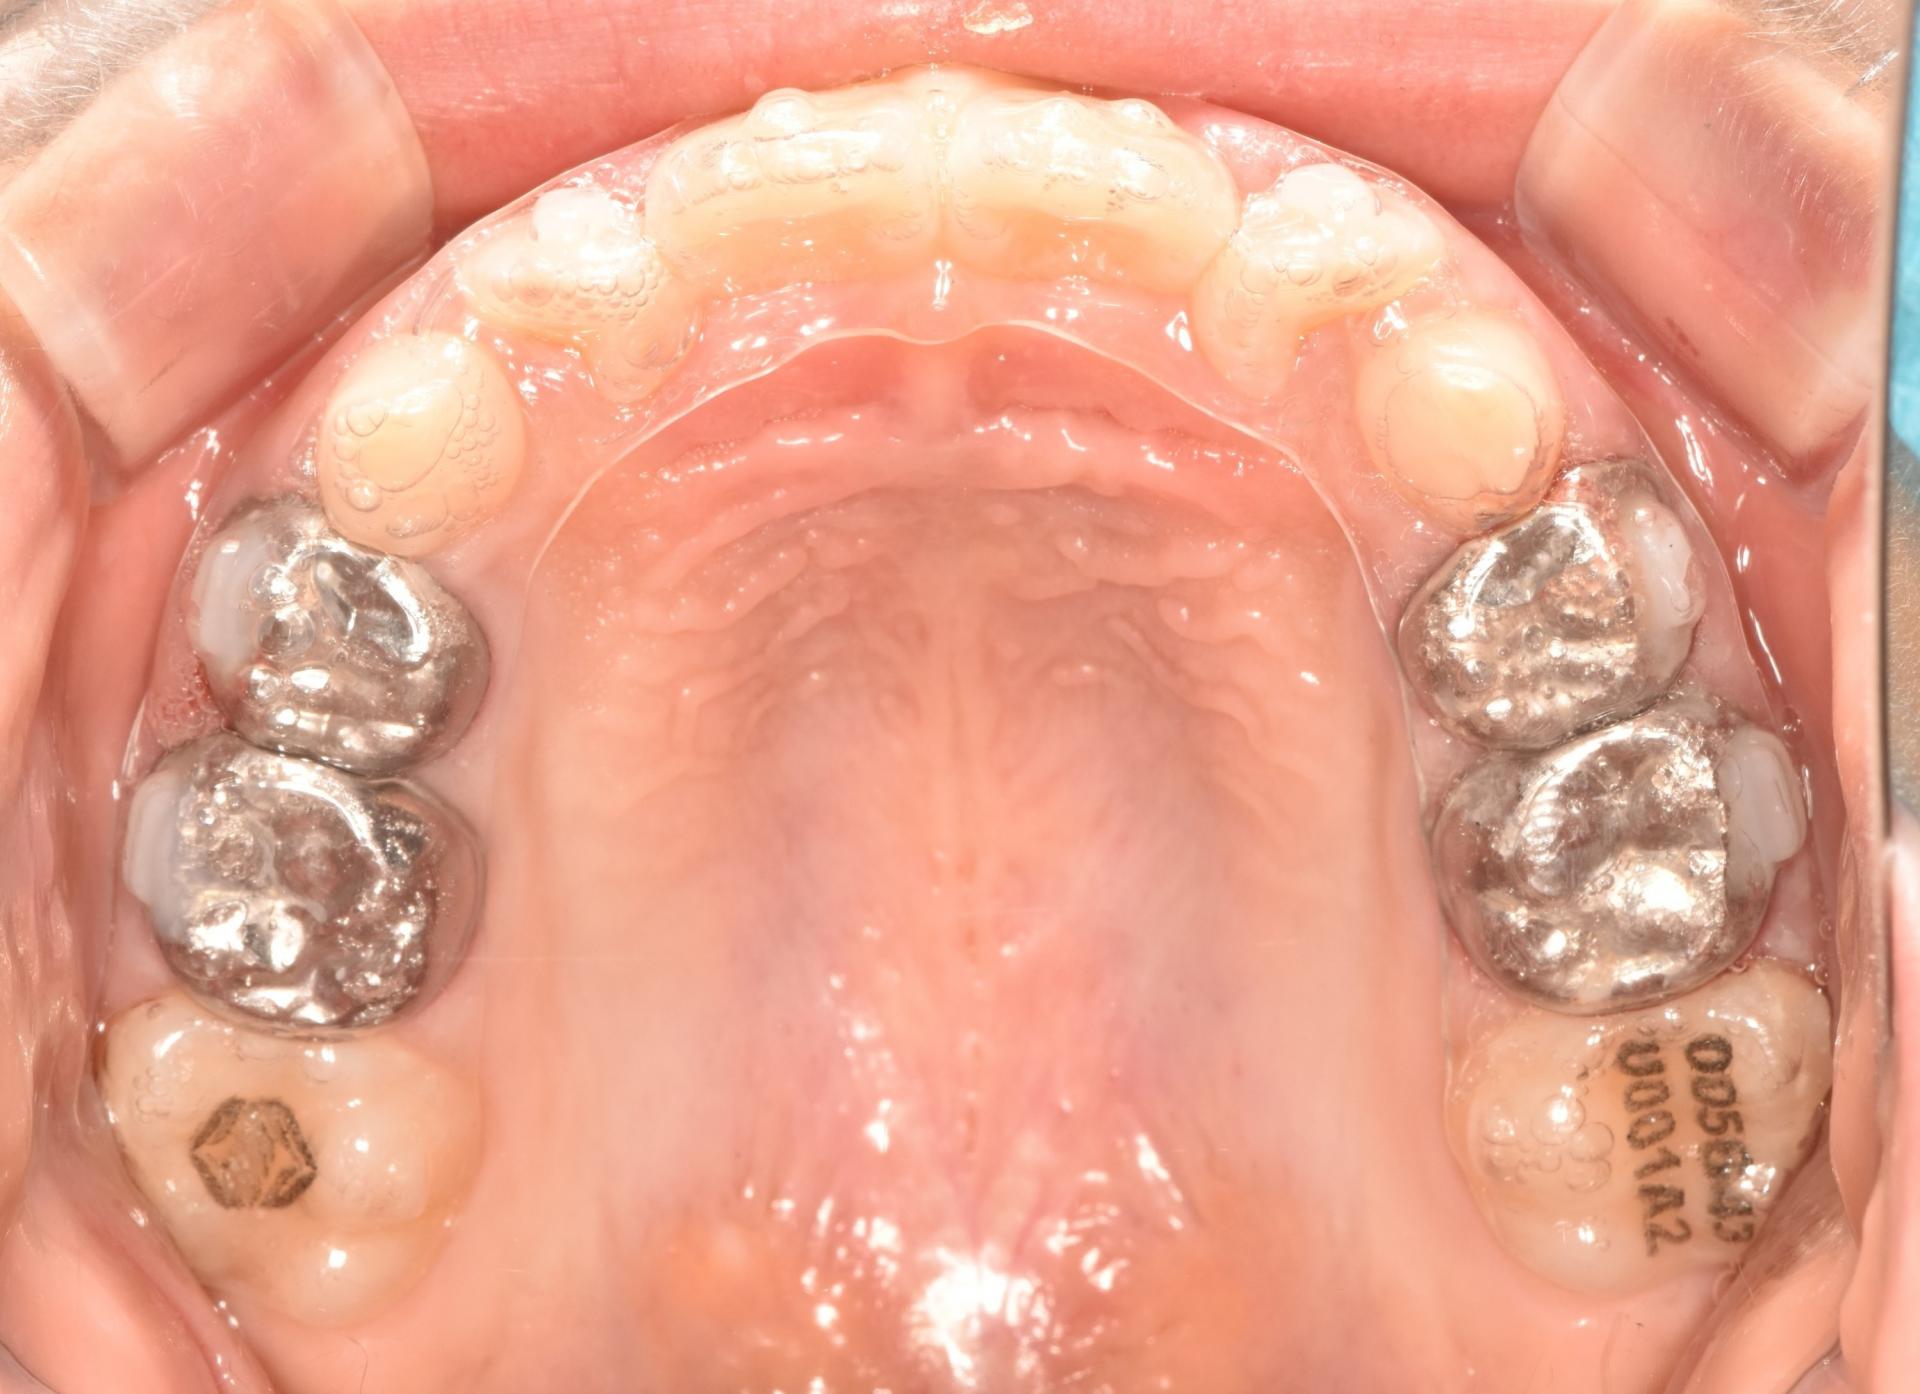

초진입니다. 위아래 앞나의 공간부족으로 이가 삐뚤뺴뚤 나고있고, 앞니도 뻐드려져있네요.